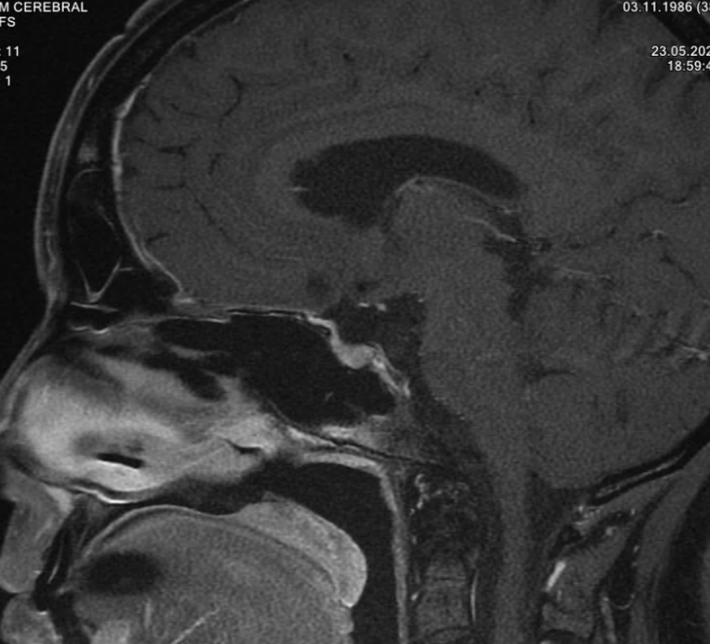

- RMN cerebral

- Monitorizare imagistică periodică (pentru tumorile mici și stabile)